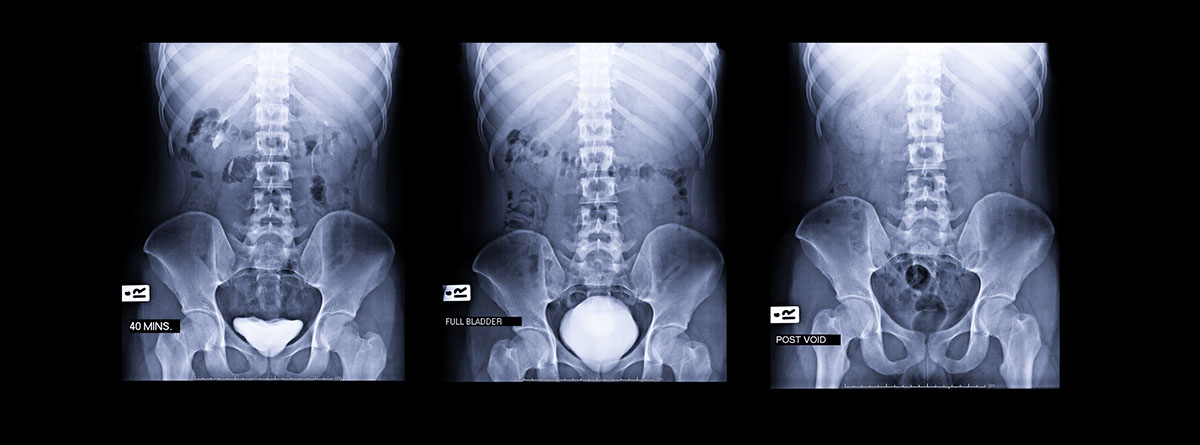

La urografía intravenosa (UIV) es una exploración radiológica, en la que, tras la administración de un contraste yodado por vena, se puede visualizar la vía urinaria en su totalidad ya que distinguimos el límite del tejido renal, el sistema pielocalicial, ambos uréteres y la vejiga. Si se realiza una placa miccional se puede visualizar hasta la uretra.

- Inicialmente se toma una radiografía simple de abdomen y posteriormente se inyecta contraste por vía intravenosa. Se realizan radiografías seriadas entre 5-20 minutos para identificar distorsiones o defectos de la vía urinaria. Incluso se pueden realizar, si fuera preciso, placas muy retardadas a los 60 o 120 minutos, cuando el riñón está enlentecido en su función.